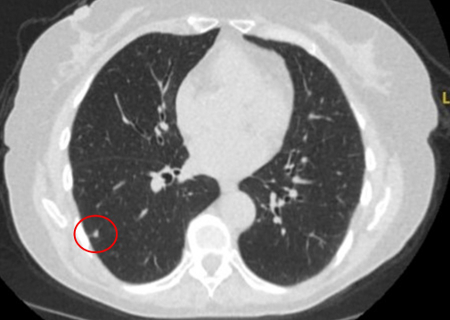

Solid nodules: volume doubling time of >600 days does not require follow-up, while a volume doubling time of <400 days, or clear growth defined as an increase in volume of 25% or more, suggests diagnostic investigations are required.[Figure caption and citation for the preceding image starts]: Computed tomography (CT) showing a right upper lobe spiculated solitary nodule within emphysema, in a current smoker with previous asbestos exposure. Note the visible pleural plaque on the left side. Resection histology revealed adenocarcinoma of the lungFrom the collection of Dr George Tsaknis, MD, PhD, FRCP(London), MRQA, MAcadMEd, PGCert; used with permission [Citation ends].